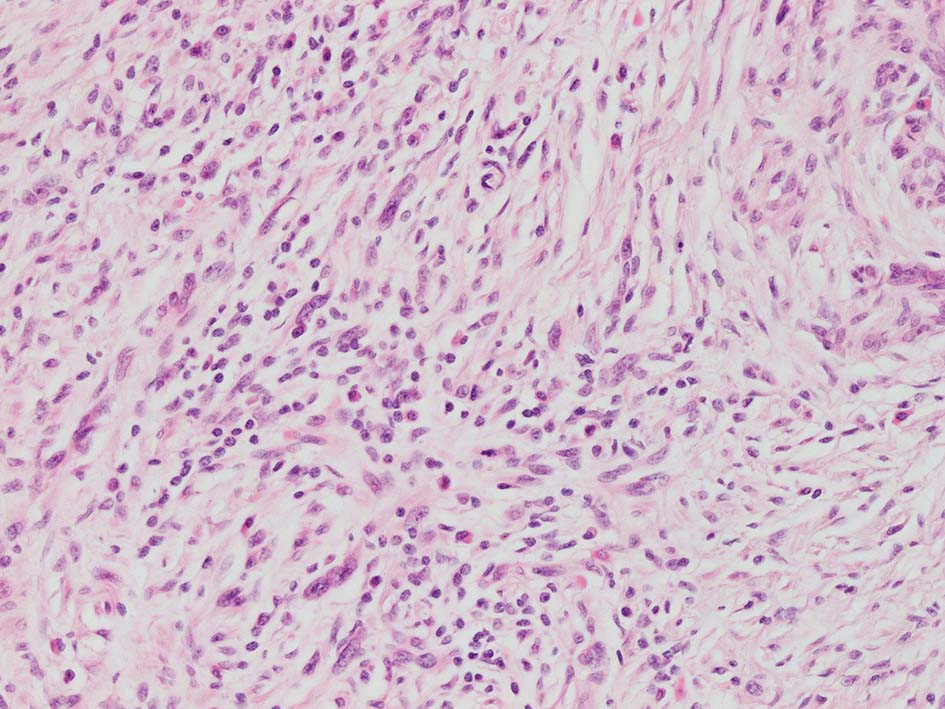

紡錘形異型メラノサイトが著明な間質反応(desmoplasia)を伴い増殖する特殊な色素性病変。*1. desmoplastic neurotropic melanomaは, desmoplastic melanomaのうち神経向性(neurotropism:神経周囲侵襲像)がめだつものでReedら*2が最初に報告した。

いずれも腫瘍細胞の異型性が乏しく, 背景の間質反応がめだつこと, メラニンの存在が目立たないことが特徴である。

“このため両者を臨床的にも病理学的にも色素性病変と診断することが困難”であり, 初回生検時には瘢痕病変や皮膚線維腫などと誤認されることが多い。

病理組織所見*4